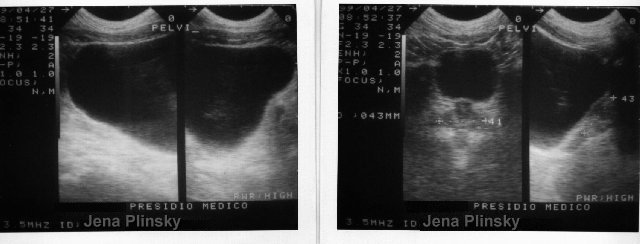

la pelvi...ci si aspetterebbe una prostata purulenta...invece � quella di un adolescente! |